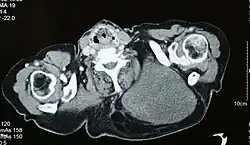

Vom makroskopischen Bild her sind Liposarkome oft relativ gut und häufig sogar kapselartig begrenzte, knotige oder gelappte, gelbliche bis grau-weiße Tumoren, die je nach Lokalisation eine erhebliche Größe und ein Gewicht von mehreren Kilogramm erreichen können. Die scheinbar gute Abgrenzung kann sich insofern als trügerisch erweisen, als in der Umgebung des Haupttumors zuweilen kleinere Tumorabsiedlungen gefunden werden. Liposarkome finden sich bevorzugt im tiefen Weichgewebe der unteren Extremität (59 %), der oberen Extremität (16 %), dem Retroperitoneum (15 %) und dem Körperstamm (8 %). Besonders häufig sind die Oberschenkel betroffen (41 %).[12]

Bildgebende Verfahren wie die Computertomographie, die Magnetresonanztomographie, die Angiographie oder die Szintigraphie liefern diagnostische Hinweise und ermöglichen eine Einschätzung der Ausbreitung des Tumorleidens. Zur definitiven Diagnosesicherung ist in der Regel eine Biopsie und die histologische Untersuchung des gewonnenen Tumorgewebes durch einen Pathologen erforderlich.